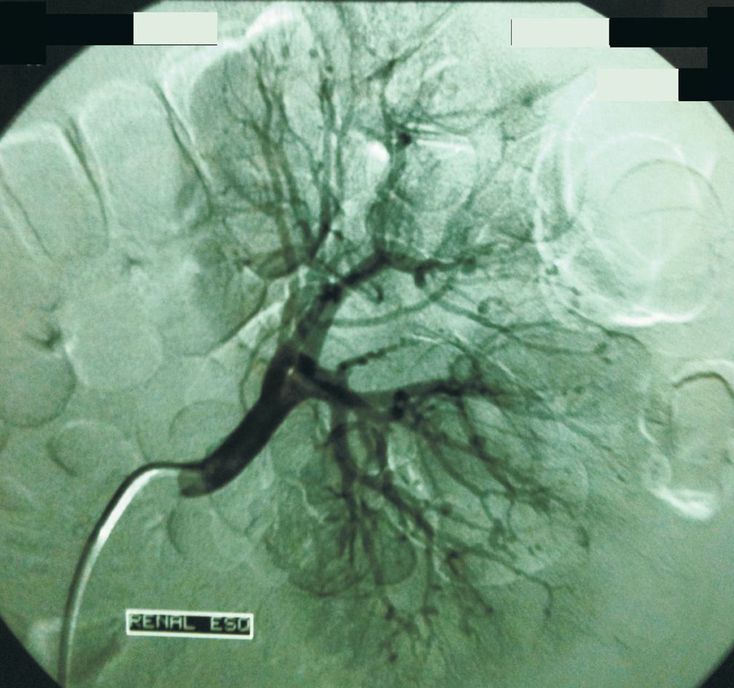

A 38-year-old patient presented to the hospital with a 2-month history of fever, malaise, weight loss, and progressive weakness on both sides of his body. Because of weakness in the dorsiflexors of his feet and toes, the patient had a high-stepping gait, lifting his knees to avoid dragging his toes on the floor (see video). The differential diagnosis of this subacute peripheral motor polyneuropathy is broad, including chronic inflammatory demyelinating polyradiculoneuropathy, diabetic neuropathies, lead intoxication, paraproteinemias, alcoholic neuropathy, nutritional deficiencies, infectious diseases, paraneoplastic syndromes, porphyric neuropathy, and amyotrophic lateral sclerosis. In this patient, electroneuromyography revealed severe mononeuritis multiplex. Laboratory tests showed an elevated erythrocyte sedimentation rate of 120 mm per hour (estimated by the Westergren method), and multiple aneurysms were seen on angiography of the kidney (as shown above), findings consistent with polyarteritis nodosa. Treatment with prednisone and cyclophosphamide led to control of the patient's fever and malaise, with normalization of the erythrocyte sedimentation rate. The patient's gait remained abnormal, however, despite rehabilitation therapy.